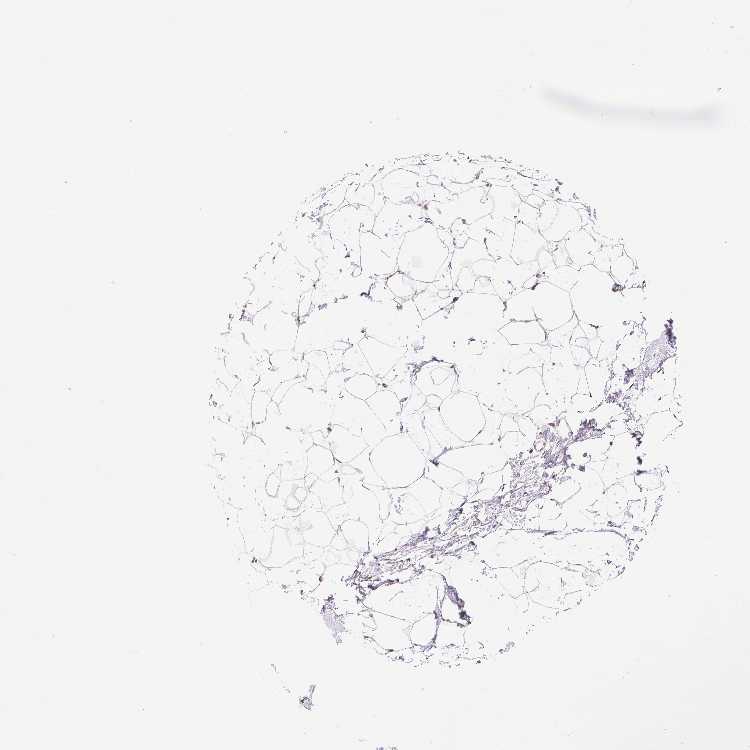

BREAST - Antibody stainingi

Antibody staining in the annotated cell types in the current human tissue is reported as not detected, low, medium, or high, based on conventional immunohistochemistry profiling in selected tissues. This score is based on the combination of the staining intensity and fraction of stained cells.

Each image is clickable and will lead to virtual microscopy that enables deeper exploration of all samples and also displays staining intensity scores, fraction scores and subcellular localization as well as patient and tissue information for each sample.

Antibody HPA037674Antibody HPA059332

Adipocytes Not detectedNot detected

Glandular cells LowMedium